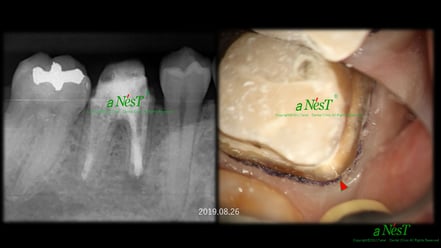

左図を拡大するとよくわかりますが、矢印の部分に確かに破折線がみえます。抜歯宣告を受けて当院を受診された方ですが、これは抜歯にはなりません。

このように、ヒビが見えるだけで、抜歯→インプラントとなるケースが、多くみられるようになってきました。

顕微鏡や動画による説明は、抜歯に誘導するツールではありません。治療のために使う重要なツールです。